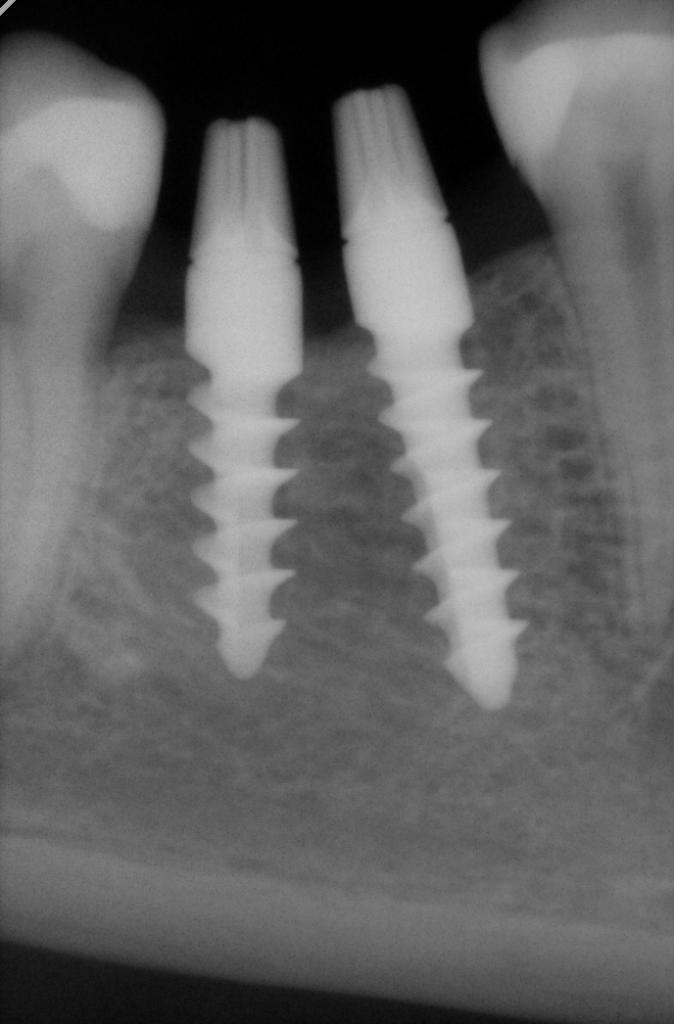

...не вдаваясь в дискуссию, что сколько стОит и почему так дорого, могу сказать, что при отсутствии 3-х больших жевательных зубов 2-х имплантов действительно маловато, если, конечно с противопоставленной стороны (антагонистов) зубной ряд не заканчивается шестым зубом...

...одно из правил классической имплантологии гласит, что имплантами должно быть замещено не количество утраченных зубов, а количество утраченных корней зубов. Поэтому при утрате 6-го и 7-го зубов подряд минимум рекомендую поставить 3 импланта, а если есть место и финансы, то и 4)) Если позволяет место, в 90% случаев вместо удаленной шестерки ставлю 2 импланта. К слову, один раз видел, как один гуру-хирург показывал рентген, где вместо удаленной верхней шестерки было поставлено 3 импланта по лункам удаленных корней))

Вложение 12983918

Вложение 12983919

А коронок сколько ставится?